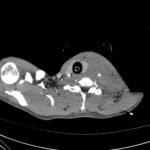

Penetrating wounds to the neck occur in 5-10% of trauma cases and are associated with very high mortality due to proximity to and involvement of vital structures. Emergent airway management and rapid diagnosis in these injuries are essential for life-saving treatment. This case study presents the case of a stab wound to the neck in an adult patient which elicited major concern for cardiovascular, neurological, and airway compromise. In such a high-risk trauma airway, this case shows the importance of keeping a wide differential and the value of expeditious management to prevent anoxic brain injury and stroke. The rapid diagnosis of a left common carotid artery transection and subsequent surgical repair were essential in this patient’s full neurological recovery.

Trauma, stab wound, neck hematoma, deviated trachea, carotid artery injury, carotid artery transection.